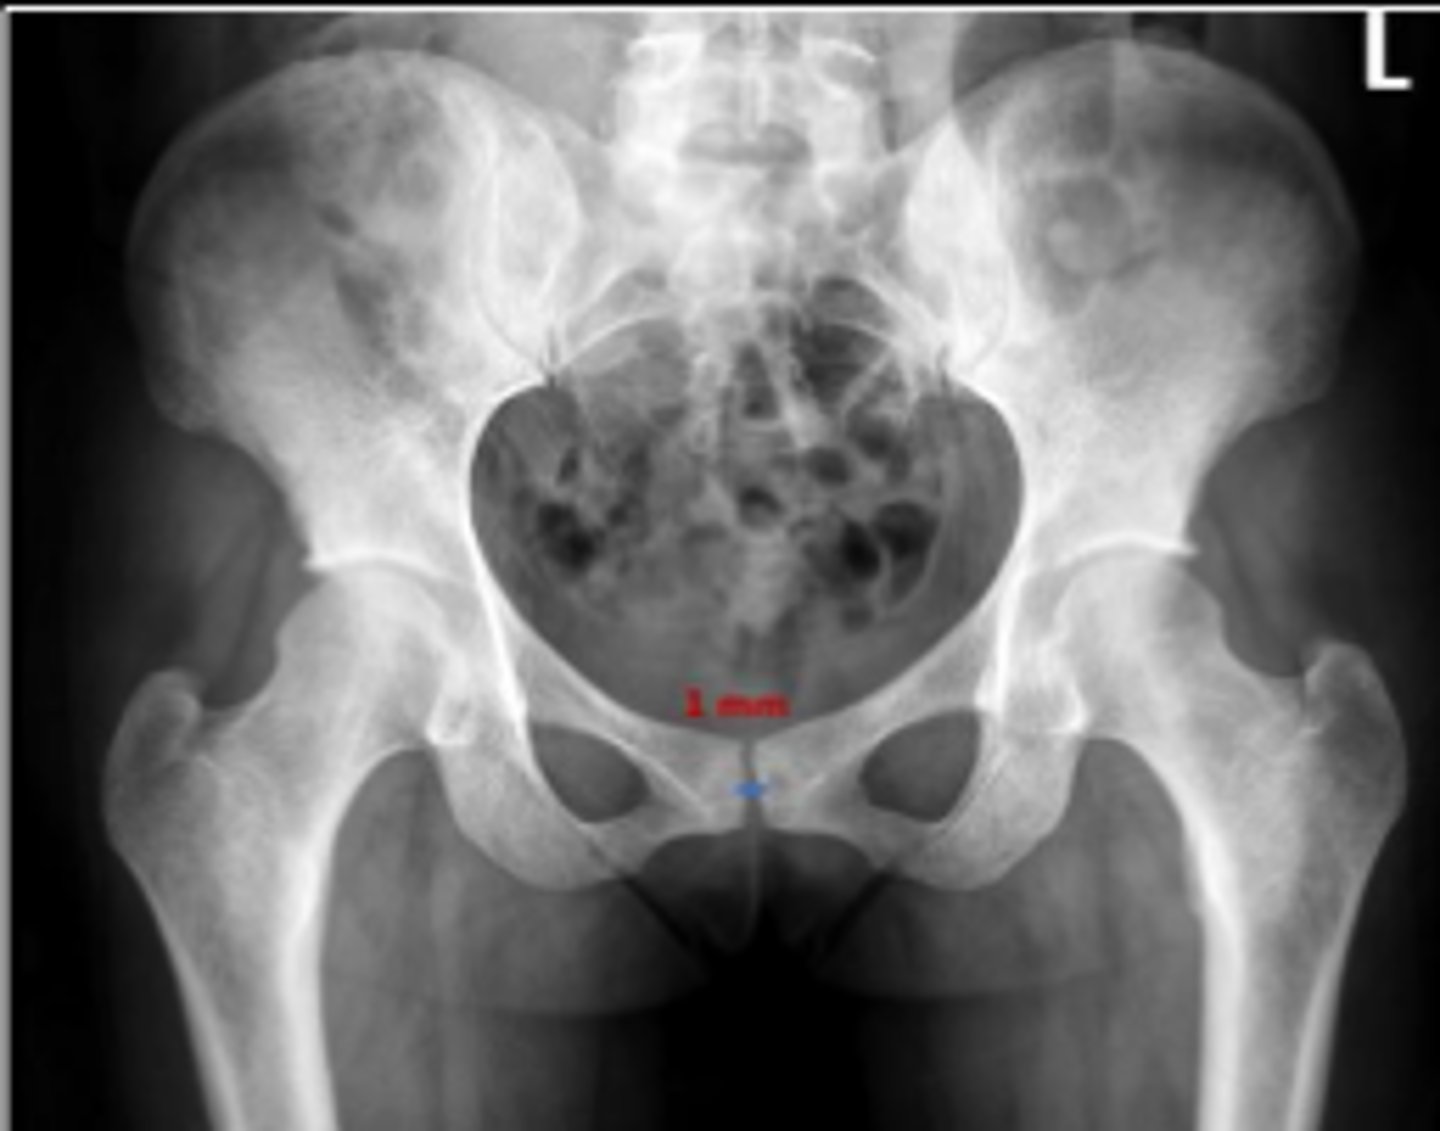

AP pelvis or bilateral hips

What is the name of the radiographic view?

Pubic symphysis width

What is the name of the assessment?

3.8-6mm (average of 5mm)

What is the normal range for this assessment in women?

The distance between the articular surfaces of

the middle of the pubic symphysis

What are the osseous landmarks for this assessment?

No

Is the measurement within normal limits?

Post-traumatic diastasis, inflammatory resorption

Name 2 conditions that may result in a measurement of 12 mm?

Name the radiographic view